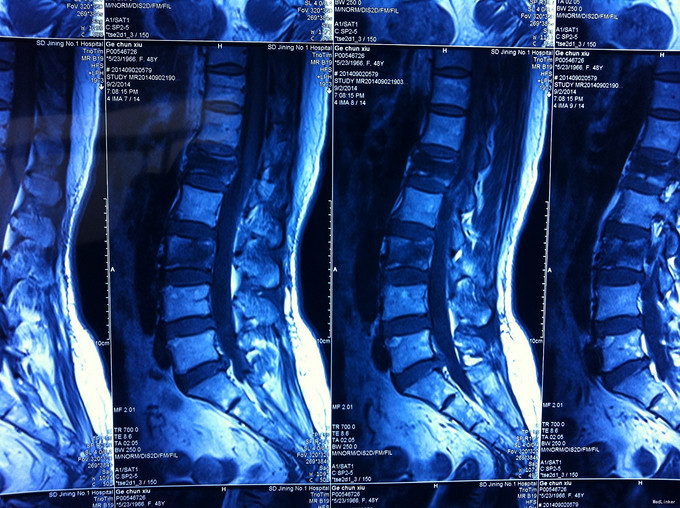

专科查体无下肢神经损伤表现:腰部叩痛,腰部活动受限,双下肢感觉无异常,双下肢肌力4-5级,双侧膝腱反射++,跟腱反射+,双侧巴氏征阴性, X-ray:腰1椎体骨折,累及前中柱,腰3椎体骨折。CT:腰1、3椎体骨折,累及中柱。MR:腰1、3骨折,新鲜骨折。影像学检查提示腰1椎体骨折较重。

诊断:腰椎骨折 腰1、3椎体 处理:1、完善相关辅助检查,明确诊断,有无手术指证; 2、完善手术评估,有无手术禁忌,手术风险及并发症; 3、在全麻下行腰1椎体后路撑开复位内固定术,腰3椎体压缩较轻,可卧床保守治疗。